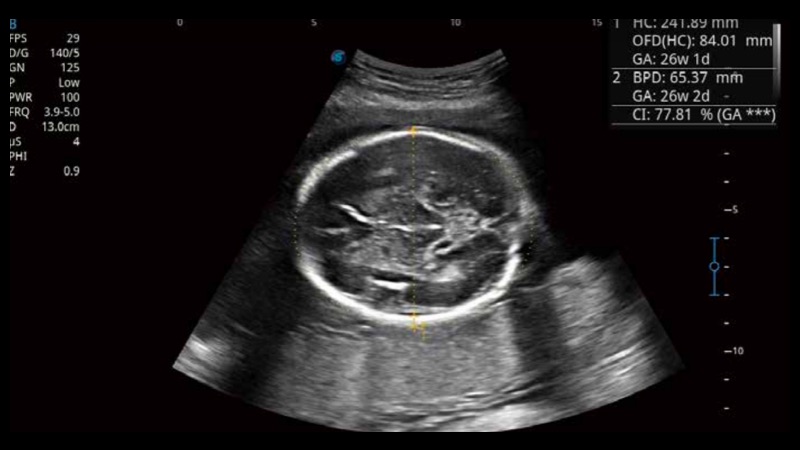

S-Fetus基于大數據深度學習算法,能夠幫助您在產前篩查過程中智能識別胎兒標準切面、自動測量并錄入報告。一個按鍵,即可智能、精準、高效地獲取胎兒生理指標,極大簡化您的產科檢查操作。

可快速對產科掃查切面完成胎兒生理學參數的自動測量,減少操作者按鍵次數,大幅提升檢查效率。